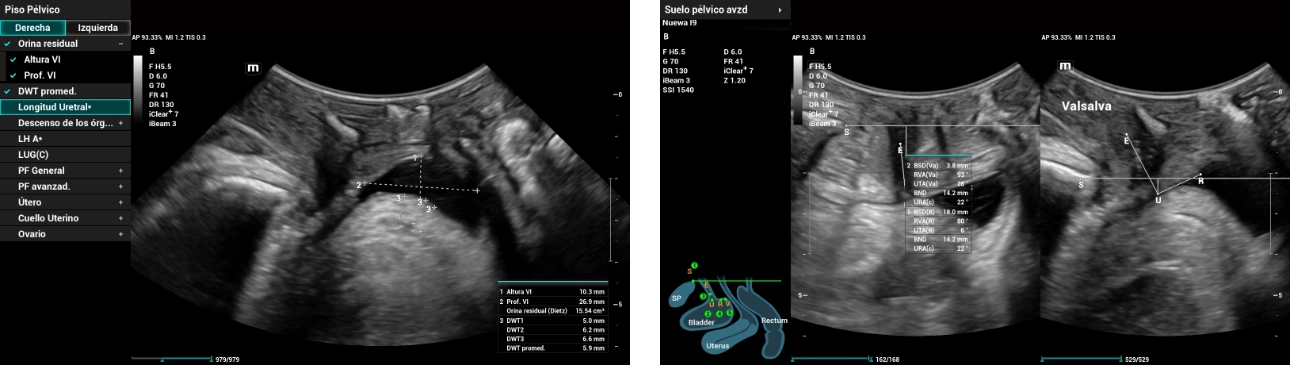

In the 2D scanning, we found the following results: Residual urine of 291ml, mean detrusor wall thickness (DWT) of 3.6mm within normal values. Bladder neck descent 22mm, α angle (URA) of 34°, β angle (RVA) of 67° (closed) and no presence of Funneling. Findings indicating Fixed urethra.

Figure 1: Evaluation of anterior compartment

During the evaluation at the periurethral level, an image suggestive of Sling with a horizontal vector (Trans obturator) was found, located in the middle third of the urethral; with the following measures:

Distance to the urethra (R) 2mm; distance to urethral meatus 16mm (R), 11mm (Val); distance to bladder neck 11mm (R), 8mm (Val), sling pubis GAP 18mm (R), 14mm (Val). No mesh presence. These findings are indicators of a Sling located at the level of the middle urethral third with measurements within the expected range.

In evaluating pelvic organ descent, we obtain bladder neck descent of 17mm below pubic symphysis, uterus N/A, and rectal ampulla 2mm above pubic symphysis. No presence of rectocele and weak pelvic floor muscle contraction.